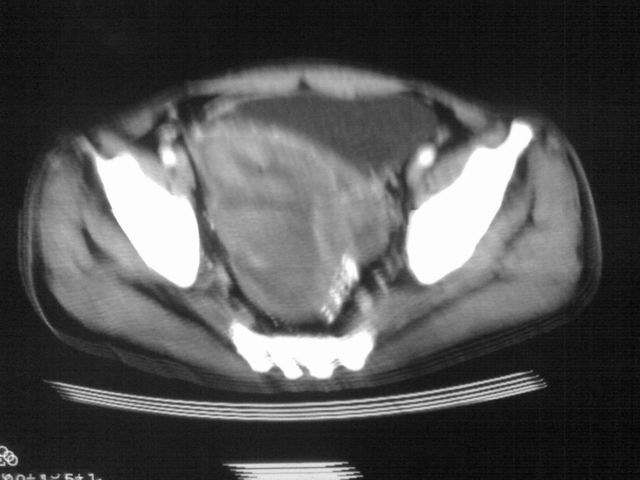

患者m 56岁,盆腔及下腹部胀痛半年,加重1月余,消瘦\中重度贫血.(附:平扫时直肠的高信号为,残留的钡剂).补一下病史:胃镜及纤维结肠镜均无明显异常.

首先是病灶的定位,平扫看很象肠管肿瘤但既然纤维结肠镜正常就可以除外结肠病变,增强成不均匀强化,位于右下腹部应该首先考虑回肠末段占位性病变,1淋巴瘤,2间质瘤,3腹膜后神经原肿瘤待除外,

首先是病灶的定位,平扫看很象肠管肿瘤但既然纤维结肠镜正常就可以除外结肠病变,增强成不均匀强化,位于右下腹部应该首先考虑回肠末段占位性病变,以间质瘤或淋巴瘤可能性大.,